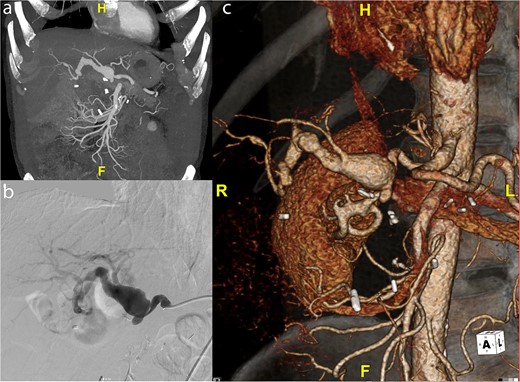

(a) Intraoperative picture of completed saphenous vein bypass to left and right hepatic arteries. (b) One-year postoperative CT scan of patent hepatic artery bypass.

Post-operatively the patient suffered no changes in biomarkers or any significant complications. He underwent a CT scan, which demonstrated a patent bypass graft prior to discharge on post-operative day 7. A 1-year CT scan demonstrated a widely patent graft to the right hepatic artery but the branch sewn to the left hepatic artery had gone on to thrombose; however, there were no clinical sequelae (Fig. 2b).